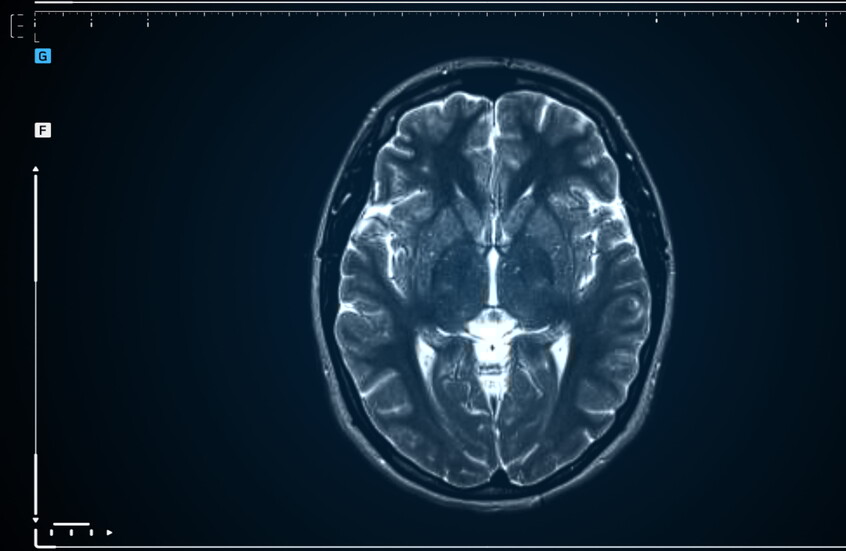

نجح علماء في الحفاظ على أنسجة الدماغ عبر تجميدها في درجات حرارة منخفضة للغاية، ثم استعادة نشاطها الوظيفي بعد الذوبان، وفقا لدراسة جديدة.

فبعد تبريد جزء من دماغ قارض مسؤول عن الذاكرة إلى 130 درجة تحت الصفر، عادت الخلايا العصبية لتتبادل الإشارات الكهربائية وتظهر مؤشرات على التعلم، بحسب نتائج الدراسة التي نشرت نتائجها مجلة Proceedings of the National Academy of Sciences.

واختبر الفريق نجاح طريقته على أقسام من الدماغ. واستخدم هذه الطريقة لتبريد جزء من دماغ القارض، وهو الحصين، إلى -130 درجة مئوية. ويلعب هذا الجزء دورا مهما في تخزين محتويات الذاكرة.

ويقول جيرمان: "كنا قادرين على إثبات باستخدام صور المجهر الإلكتروني أن البنية النانوية للنسيج لم تتغير بسبب عملية التجميد. وبعد الذوبان، تشكلت إشارات كهربائية تلقائيا مرة أخرى في الحصين، وانتشرت بشكل طبيعي عبر الشبكات العصبية".